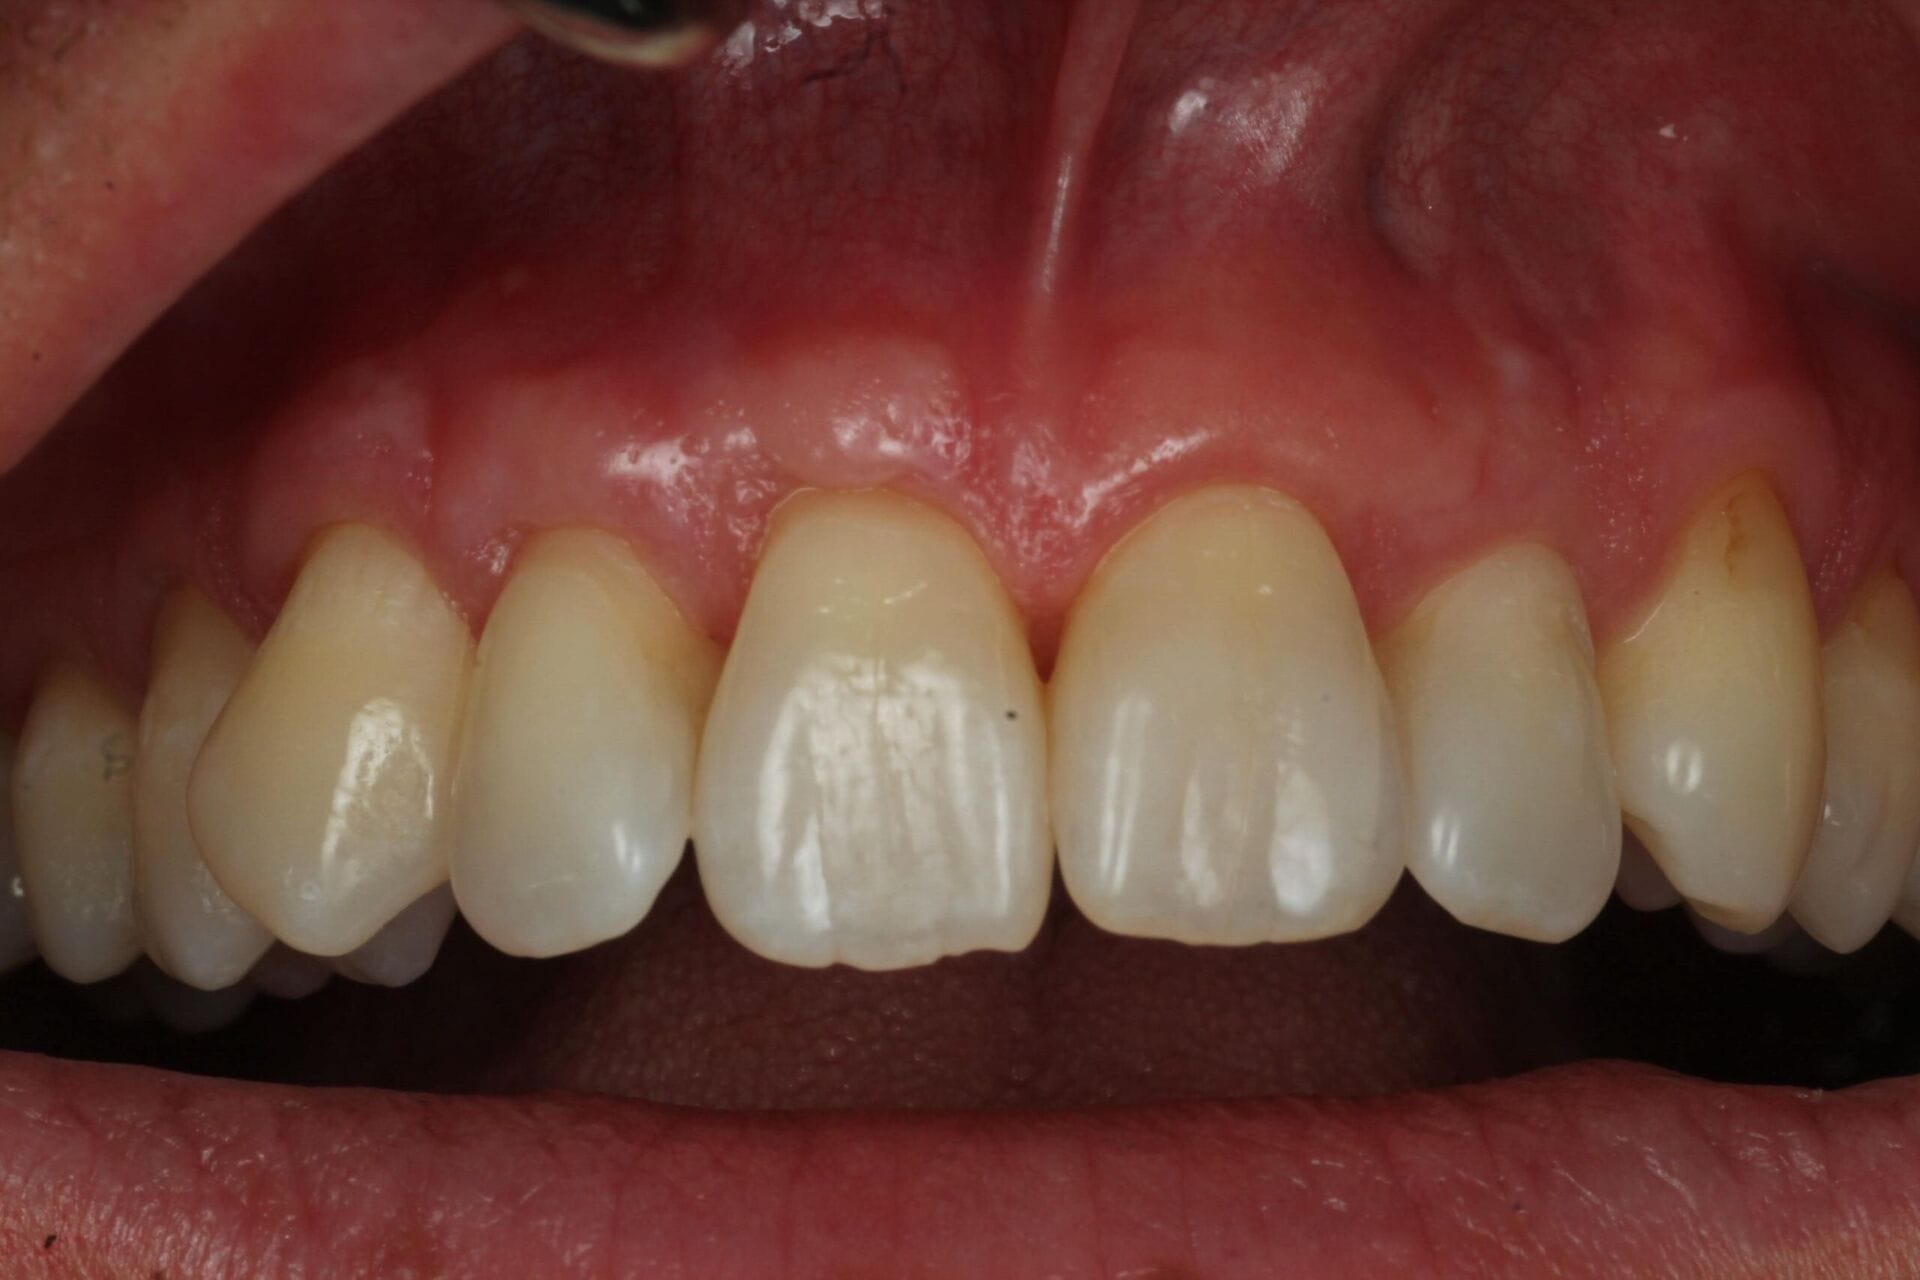

Gum disease, or periodontal disease, is a common but serious condition that affects the soft tissues and bone supporting your teeth. It typically starts with gingivitis; swollen, red, or bleeding gums caused by the buildup of plaque and tartar. If untreated, it can progress into periodontitis, leading to gum recession, bone loss, and even tooth loss.

Periodontitis is the advanced form of gum disease. It develops when inflammation from untreated gingivitis spreads below the gumline, destroying the connective tissue and bone that anchor your teeth. Symptoms can include:

Gum recession